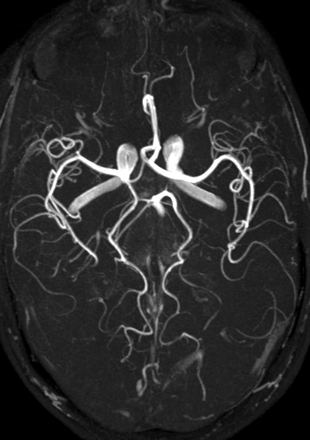

MR angiography (MRA) is one of the most significantly improved MR techniques at higher field strength (42–46). Regarding time of flight (TOF) imaging (Fig 15), longer T1 times at 3T have the effect that the signal intensity inside the vessels is preserved even with thicker sections and in smaller vessels. Moreover, SNR is significantly increased, making higher resolutions possible within reasonable acquisition times (47). This results in better diagnostic quality—for example, with respect to intracranial aneurysms (48, 49).

Maximum intensity projection of a time-of-flight angiography (TR, 28 ms; TE, 4.92 ms; matrix, 704 × 576; FOV, 163 × 200 mm2; 92 sections; section thickness, 0.75 mm; bandwidth, 105 Hz/pixel; flip angle, 25°) at 3T showing the clear depiction of even very small vessels.